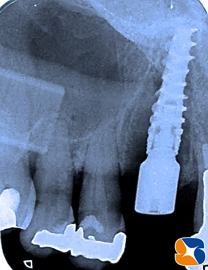

歯科用CTで患者様の骨の状態を診断します。糸切り歯(犬歯)のほっぺた側の骨が、全て失われている状態でした。インプラントを断られるのも無理はありません。

(1)犬歯の抜歯および腫瘍の塊を骨から剥がし取りました。CT画像から、この状況は把握出来ていましたので慌てることはありません。全て予定通りです。いよいよインプラントの移植と骨の造成が始まります。

(2)インプラントの先端の僅かな骨を頼りに移植を試みます。

使用インプラントメーカー:ノーベルバイオケア社製のアクティブ直径4.3㍉×13㍉